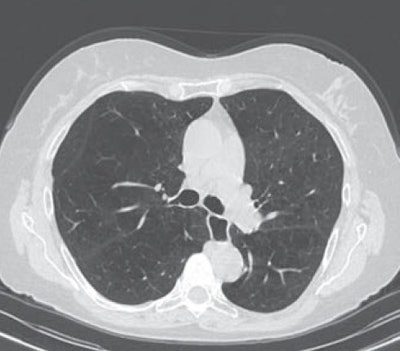

To see if AI could accurately quantify emphysema, the researchers used a deep image-to-image network -- a multilayer convolutional neural network that had been trained and tested on more than 10,000 CT datasets acquired on scanners from three vendors at over 20 clinical sites in the U.S. and Europe. Approximately 25% of these datasets were from patients with emphysema.

The algorithm was retrospectively evaluated on 141 patients who had received unenhanced chest CT and spirometry measurements within six months of each other at MUSC between August 2017 and July 2018. All CT exams had been acquired on one of three scanners from Siemens Healthineers: Somatom Definition Flash, Force, or Emotion.

To determine if reconstruction methods would impact performance, the researchers applied the algorithm to two reconstruction kernels. The first method used a section thickness of 1.5 mm with a long kernel, while the second utilized a section thickness of 1.5 mm with a soft-tissue kernel. Emphysema was quantified using spatial filtering and a threshold of -950 Hounsfield units.